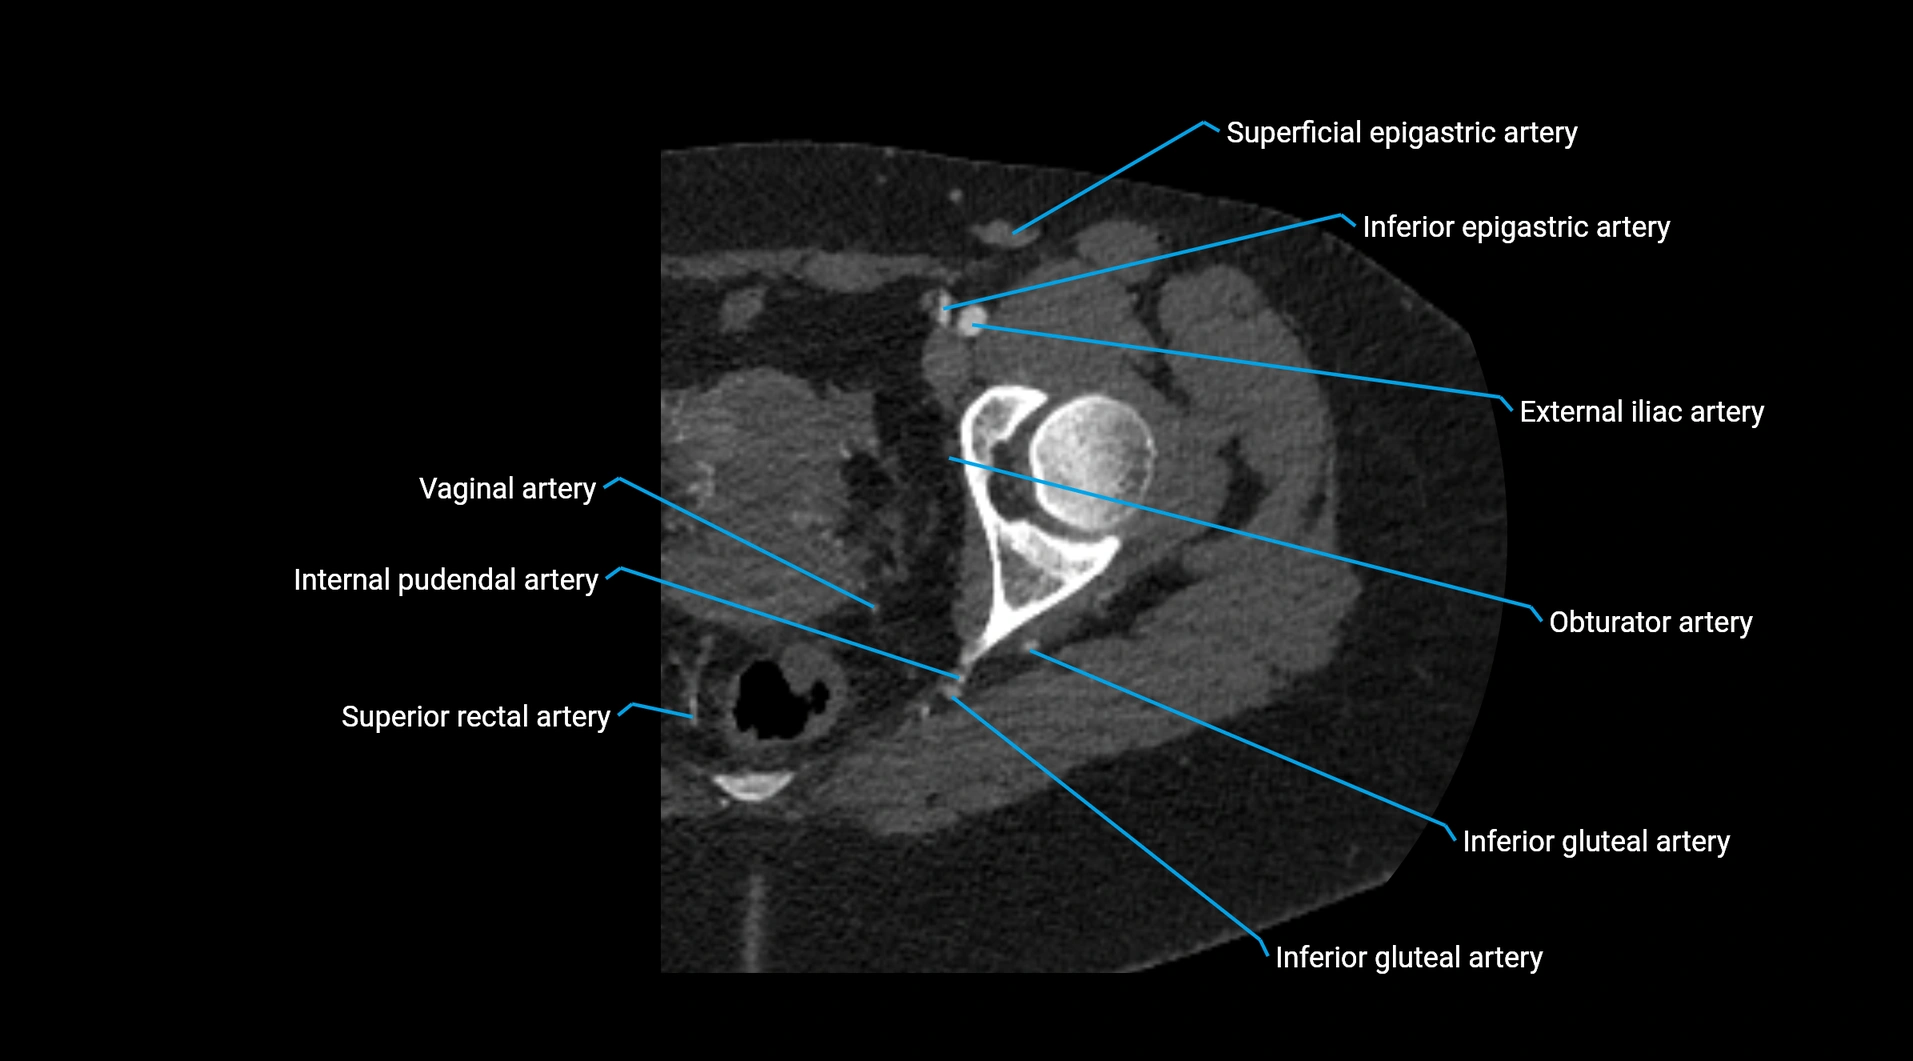

CT images

image